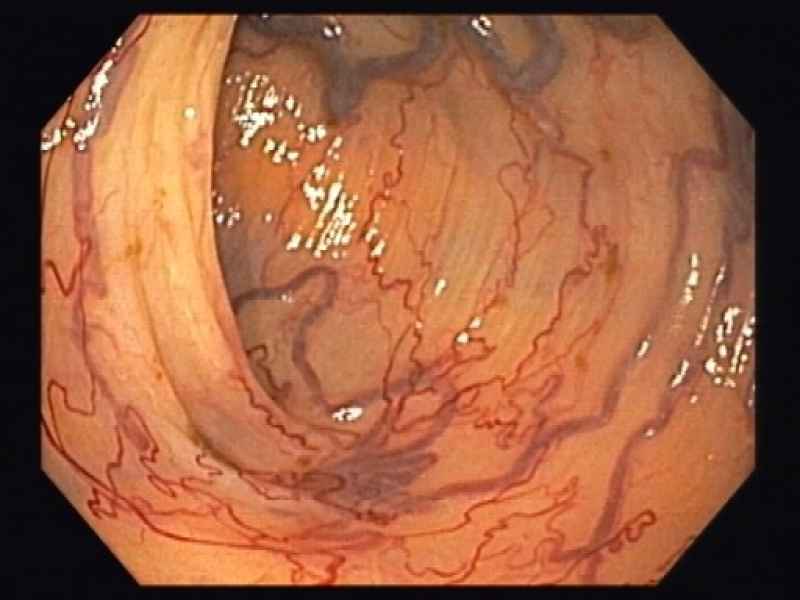

A mantle of rosaries along the colon - 2.º Prémio (Fotografia)

Fotografias